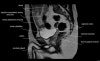

- Sagittal section

Sagittal PD fat suppression is sensitive to fluid that may be present with AVN or stress fractures.